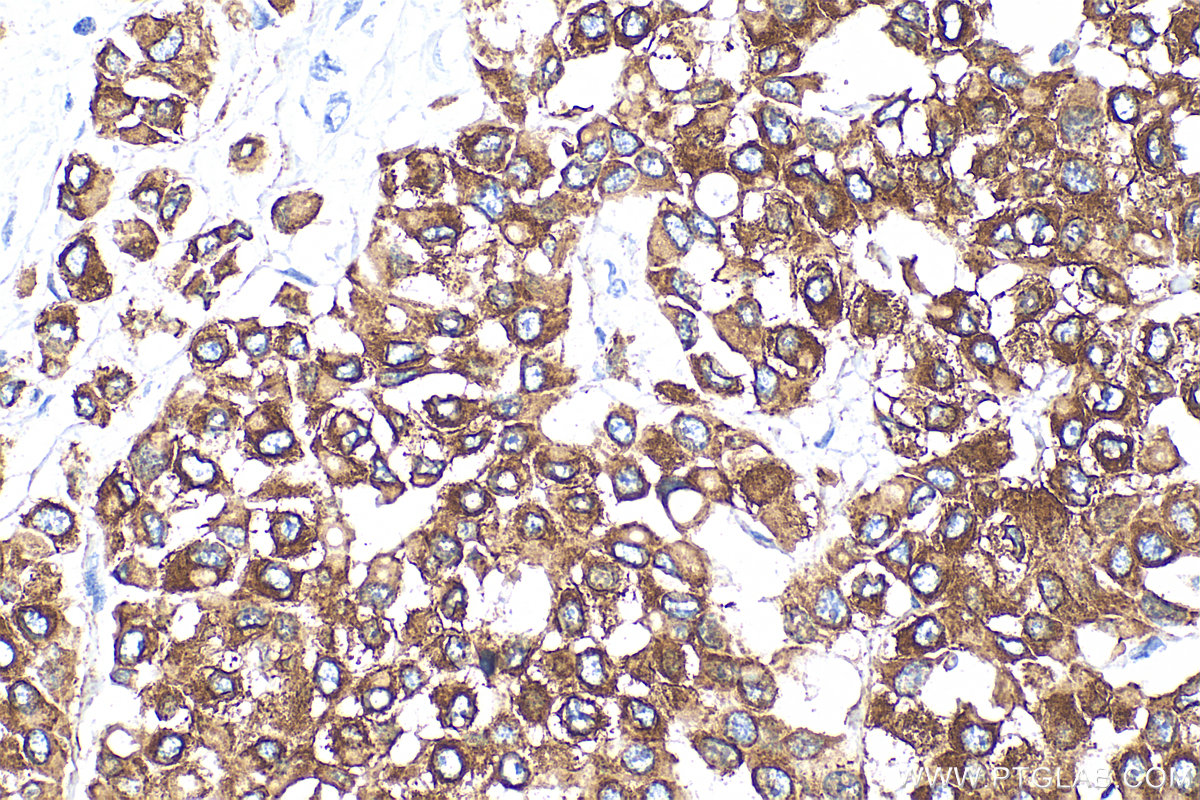

| Positive IHC detected in | human tonsillitis tissue, human appendicitis tissue, human bowen disease tissue, human breast cancer tissue, human colon tissue, human liver tissue, human renal cell carcinoma tissue Note: suggested antigen retrieval with TE buffer pH 9.0; (*) Alternatively, antigen retrieval may be performed with citrate buffer pH 6.0 |

Cytokeratin 8 (CK8) is a protein that belongs to the cytokeratin family, which is a group of structural proteins found in the intracytoplasmic cytoskeleton of epithelial cells. CK8 forms intermediate filaments within the cytoplasm of simple epithelial cells, typically as a dimer with cytokeratin 18 (CK18). These filaments provide a stabilizing framework that helps determine cell shape and enables cells to cope with mechanical stress. CK8/CK18 filaments also serve as a mesh of "paths" for signaling molecules, metabolites, and pathogens to travel within the cell in an organized manner. CK8 is expressed in various epithelial tissues and is particularly associated with glandular and simple epithelia. Its expression is also a significant marker in several types of cancer, including lung and esophageal cancer, where it can indicate tumor progression and poor prognosis.